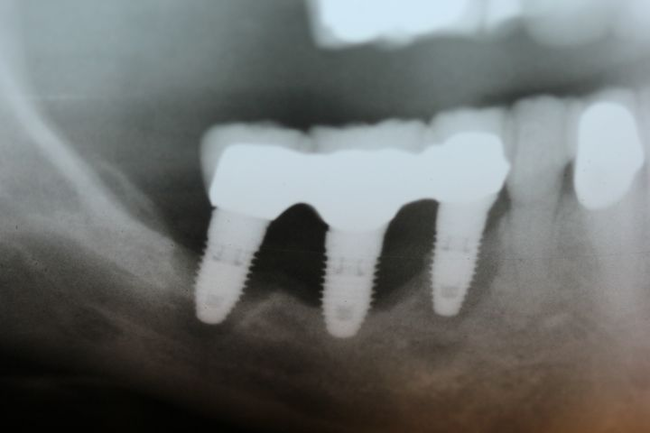

شکستن بدنه ی ایمپلنت

شکسته شدن بدنه ی ایمپلنت دندان نیز می تواند یکی از بدترین عوارض ایمپلنت دندان ها محسوب شده و اتفاقی جبران ناپذیر می باشد چرا که در صورت بروز چنین مشکلی تنها راه چاره خارج کردن ایمپلنت از طرف دندان پزشک و جراح مخصوص و سپس کاشت دوباره ی ایمپلنت می باشد. عواملی همچون فشار بیش از اندازه بر روی دندان و یا پروتز نامناسب آن ها سبب شکستگی بدنه ی ایمپلنت ها می شوند.